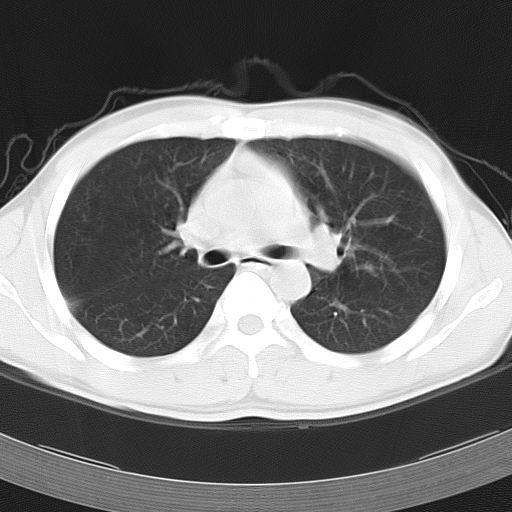

男,34岁,咳嗽2~3个月,无咳血,病初有发热。

病变分布以双上肺叶外带明显,双下肺未见异常,此一点不十分支持肺泡蛋白质沉着症,病变未见铺碎路石征,也不肺泡蛋白质沉着症。考虑间质性肺炎,结核不除外。

据报告﹐自7~8个月的婴儿至72岁的老人均有患肺泡蛋白沉积症者﹐但以30~50岁者居多。男性约为女性的3倍。鉴于约半数病人经常接触各种粉尘或有害气体﹐且以硅尘长期给鼠吸入﹐可使动物患肺泡蛋白沉积症﹐故认为本病可能是肺泡对化学性刺激的非特异性反应,导致肺泡巨噬细胞分解,产生pas阳性蛋白质。

该患者男性,34岁,进一步追问病史,该人系矿砂堆场码头工人,长期粉尘环境下工作。--这条病史符合以上特点。

ct表现 (1)中央型:表现为蝶翼状浸润性阴影对称分布于两侧肺门周围,其内可见支气管充气征,病变区与正常肺组织分界清楚。(2)外围型:表现为多发性条片状、斑片状及斑块状高密度影,弥散、对称或不对称分布于两肺或一侧肺外围部位。病变区与正常肺组织及脏层胸膜面分界清晰,呈地图样改变。hrct可显示小叶间隔增厚及肺小叶内淡淡的密度增高影等细微结构,同时易发现肺大疱、肺气囊及节段性肺不张。

再仔细阅读该病人的ct片,我们不难发现,病例所表现的正是外围型的肺泡蛋白沉积症表现,即:为多发性条片状、斑片状及斑块状高密度影,弥散、对称或不对称分布于两肺或一侧肺外围部位。病变区与正常肺组织及脏层胸膜面分界清晰,呈地图样改变。

所以,我本人的意见也是趋向于肺泡蛋白沉积症的诊断,尽管最后诊断还是要根据支气管肺泡灌洗物检查或经纤支镜或剖胸活检作出病理诊断。或痰液检验:咳出的痰经80%乙醇固定,pas染色有15%阳性的脂质。